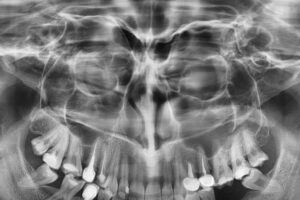

| Radiografia digitală panoramică (opt) | Tomografia Computerizată CBCT – CT 3D |

Denta Film, cabinet de radiologie dentară digitală, oferă soluții eficiente, într-un timp scurt, la un nivel minim de radiații. În cadrul acestui cabinet, pacienții pot beneficia de: radiografie digitală retroalveolară, radiografie digitală panoramică sau ortopantomografia, teleradiografie (cefalometrie), tomografie computerizată CBCT.

Cabinetul de radiologie Denta Film, situat în Cluj-Napoca, efectuează radiografii digitale 3D, radiografii cu imprimare laser de ultimă generație, oferind avantajul radiațiilor minime (cu 90% mai puţine radiatii decât în cazul unei radiografii clasice).